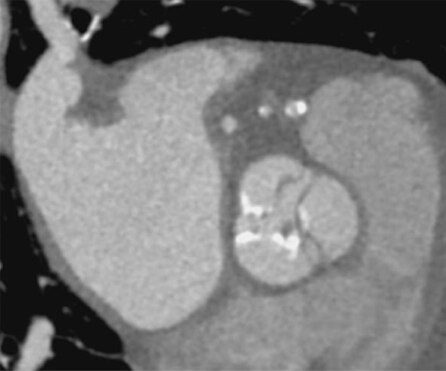

TAVI後の血栓弁の評価です。TAVI後のCTで弁葉に低吸収域を認める症例を見かけますが、この所見はHALTと呼ばれ、人工弁に付着した血栓と考えられています。HALTが大きい症例では弁葉の動きを障害することがあるため、CTでの評価は重要です。

HR82の高心拍で、モーションアーチファクトの影響が強かった症例です。SSF2.0でも金属からのアーチファクトは少し残存していますが、モーションアーチファクトが抑制され、SSF2.0 Offでは見えずらかった弁葉のわずかなlow densityをSSF2.0ONではしっかりと確認できるようになりました。